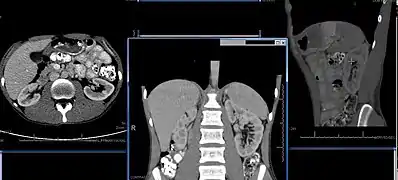

Imaging

Renal ultrasonography is essential in the diagnosis and management of kidney-related diseases.[43] Other modalities, such as CT and MRI, should always be considered as supplementary imaging modalities in the assessment of renal disease.[43]